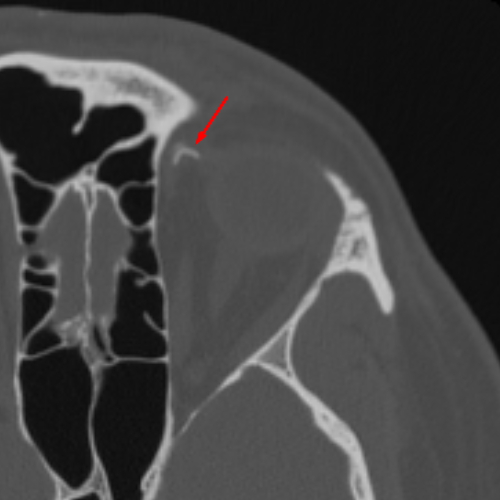

Age: 42

Sex: Male

Indication: Trauma